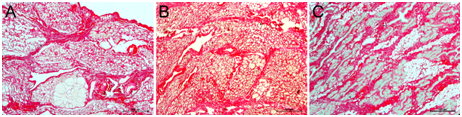

To understand the collagen density in mammary tissue of lactating, mastitic and cancerous glands, we estimated pixel intensities of collagen fiber present in epithelial and stromal compartments of mammary tissues. In lactating glands, thin rims of collagen fibers were present around the alveoli in the basement membrane (Figure 2). Thickness of collagen fiber varied depending upon the size of the alveoli. A more distended alveolus had thinner rims of collagen fiber. Fibers were loose, curly and thin in epithelial compartment. Stromal compartment collagen fibers were occupied fully except the lumen of blood vessels and empty spaces (Figure 2). In cancer tissue, collagen fibers were more straight, rigid and thick (Figure 2). In metastasis, straight and rigid collagen fibers promote invasion and migration of cancer cells.12

Figure 2 Picrosirius red (PSR) staining of lactating (A), mastitic (B) and cancer of goat mammary glands. Magnifications 400 X.